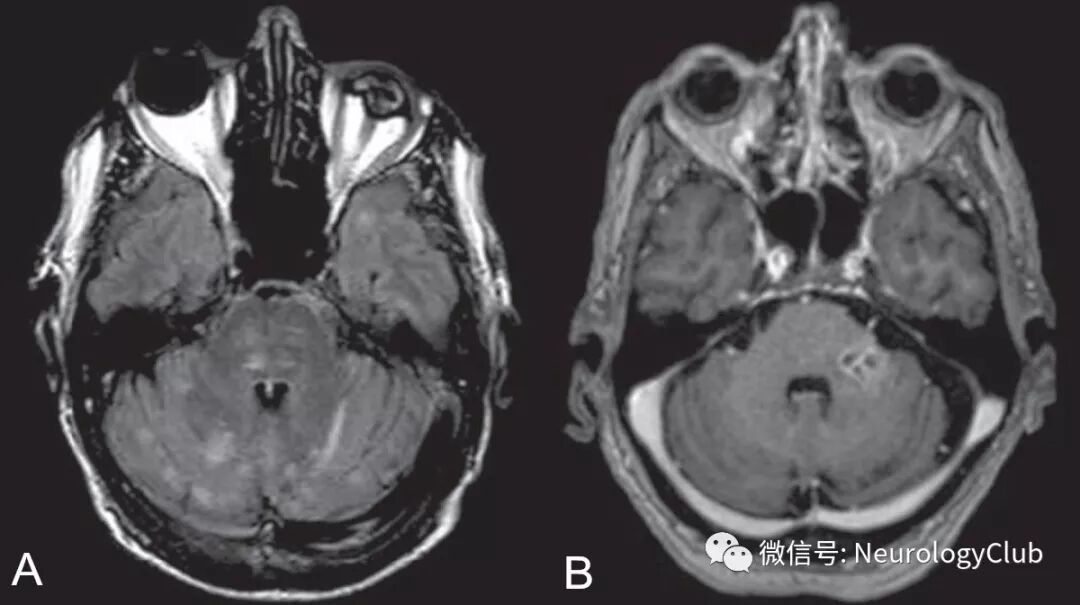

Moragas等报道的李斯特菌菱脑炎MRI异常达100%(幕下病变100%,幕上病变50%),而PNS所致菱脑炎患者MRI均正常。在病毒所致的菱脑炎中,70-75%的EV 71感染患者,50%的西尼罗河病毒感染患者,2/3合并疱疹感染患者(单纯疱疹病毒,Epstein-Barr病毒,巨细胞病毒,水痘-带状疱疹病毒和人类疱疹病毒6型)以及几乎100%的BD患者可见MRI异常信号。T2/FLAIR高信号病灶主要位于脑桥,延髓,上颈髓和小脑,而中脑累及少见。

(图1:李斯特菌菱脑炎患者;a:FLAIR可见左侧小脑中脚,小脑和脑桥高信号病灶;b:T2WI可见病灶延伸至上颈髓;c:T1增强可见左侧脑桥后外侧病灶强化;d:FLAIR上可见左侧延髓后外侧病灶)

(图3:李斯特菌菱脑炎患者;A:FLAIR可见不规则,边界不清的多发高信号病灶;B:增强T1可见左侧脑桥环形强化病灶